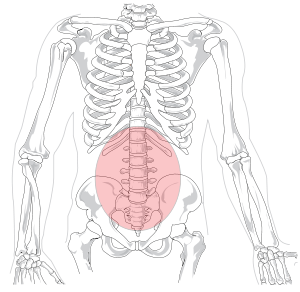

In tetrapod anatomy, lumbar is an adjective that means of or pertaining to the abdominal segment of the torso, between the diaphragm and the sacrum.

The lumbar region is sometimes referred to as the lower spine, or as an area of the back in its proximity.

In human anatomy the five vertebrae in the lumbar region of the back are the largest and strongest in the movable part of the spinal column, and can be distinguished by the absence of a foramen in the transverse process, and by the absence of facets on the sides of the body. In most mammals, the lumbar region of the spine curves outward.